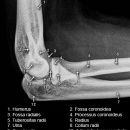

Radiusköpfchen; Greenspan

Beurteilungskriterien

Proximale Radiusfrakturen sind mit 50% die häufigsten Ellbogenverletzungen des Erwachsenen (Kinder 15%)! 50% der Radiusköpfchenfrakturen sind nicht disloziert und u.U. in den Standartprojektionen nicht nachweisbar -> bei klinischem Verdacht ist ein positives Fettpolsterzeichen in der seitlichen Aufnahme nahezu beweisend! Zusätzlich Greenspan-Aufnahme, evtl. CT oder MRT! Harmonische Darstellung des Radiusköpfchens? Impressionen? Stufe? Verdichtungen? Fissur? Knickbildung?